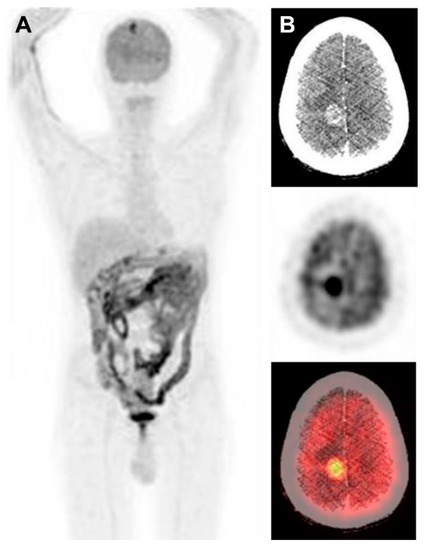

Brain Metastases Unresponsive to Immunotherapy Detected by 18F-FDG-PET/CT in a Patient with Melanoma

Fonti, R.; Pellegrino, S.; Mainolfi, C.G.; Matano, E.; Del Vecchio, S. Brain Metastases Unresponsive to Immunotherapy Detected by 18F-FDG-PET/CT in a Patient with Melanoma. Diagnostics 2020, 10, 410. https://doi.org/10.3390/diagnostics10060410